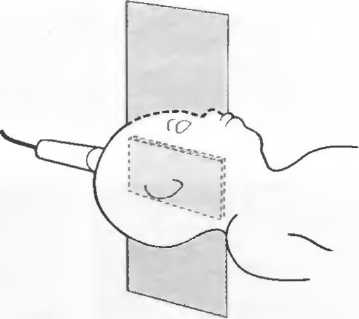

3. Ультразвуковые исследования в педиатрии. Для детей необходим датчик с частотой 5 МГц с глубиной фокусировки на 5-7 см. При исследовании мозга новорожденного используется секторный датчик с частотой 7,5 МГц с глубиной фокусировки на 4-5 см (этот датчик также используется для исследования яичек и структур шеи у взрослых).